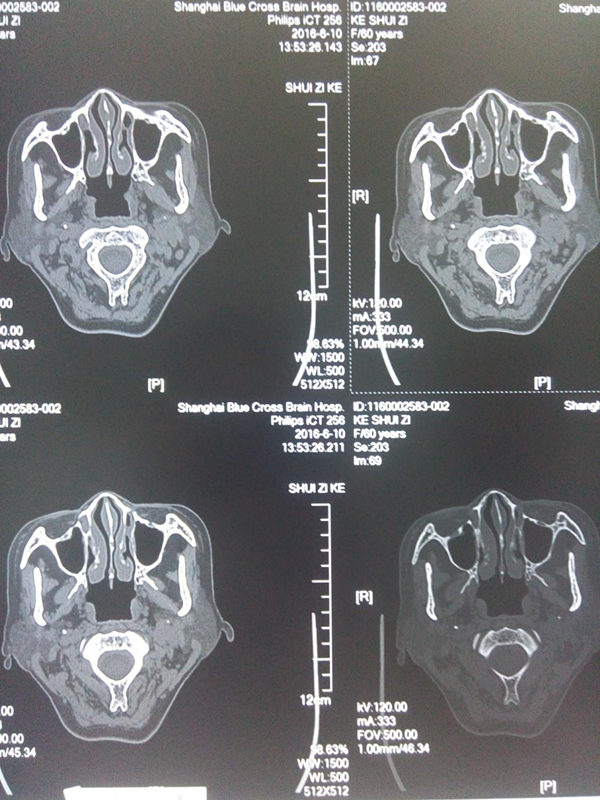

CT扫描双侧茎突无异常增生